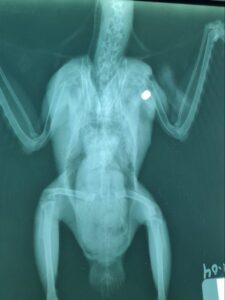

Según detalló el biólogo, “el ejemplar presentaba traumatismo del ala izquierda y un orifico en la parte pectoral donde se encontró una munición de un aire comprimido, por lo que inmediatamente fue revisado por el médico veterinario del CAFAju y posteriormente derivado para mayor observación”.